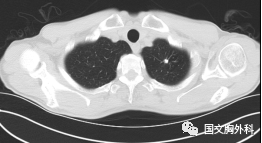

這個(gè)病人檢查胸部CT如圖3:根據(jù)影像學(xué)考慮是惡性腫瘤,行手術(shù)治療后病理回報(bào):“肺膿腫,合并炎癥纖維組織增生”,因此“肺占位”不代表就是惡性腫瘤,診斷金標(biāo)準(zhǔn)是病理診斷。如果檢查后發(fā)現(xiàn)“肺占位”先不要驚慌,及時(shí)就診請??漆t(yī)生會(huì)診指導(dǎo)治療才是關(guān)鍵。